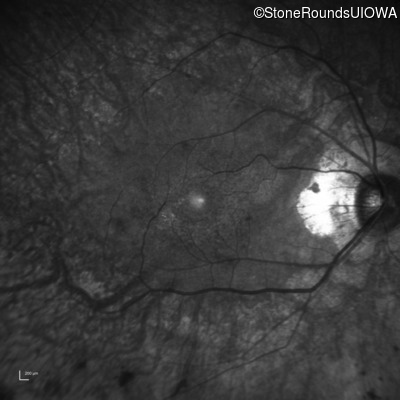

Infrared Fundus Photograph - Right - 20/25 -2 sc

Exemplar